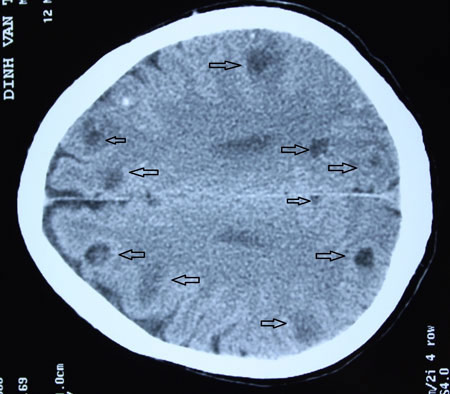

Đúng như phỏng đoán, trên hình ảnh chụp CT, mỗi lát cắt chụp đã phát hiện 4 - 5 ổ sán não, tính chung trong não người bệnh lên đến trên dưới 50 ổ sán.

TS.BS Nguyễn Như Lâm, Trưởng khoa Vi rút - Kí sinh trùng, cho biết, phần lớn bệnh nhân nhiễm sán não đến bệnh viện khám với biểu hiện đau đầu kéo dài, thậm chí có co giật, điều trị tại tuyến cơ sở nhiều tháng, thậm chí nhiều năm không đỡ với chuẩn đoán đau đầu, động kinh, nhất là ở tuyến y tế cơ sở. Nhưng khi đi chụp cắt lớp, hình ảnh nang sán não dễ dàng được phát hiện, bởi nang sán có kích thước khá to, có những nang lớn từ 0,5-1cm.